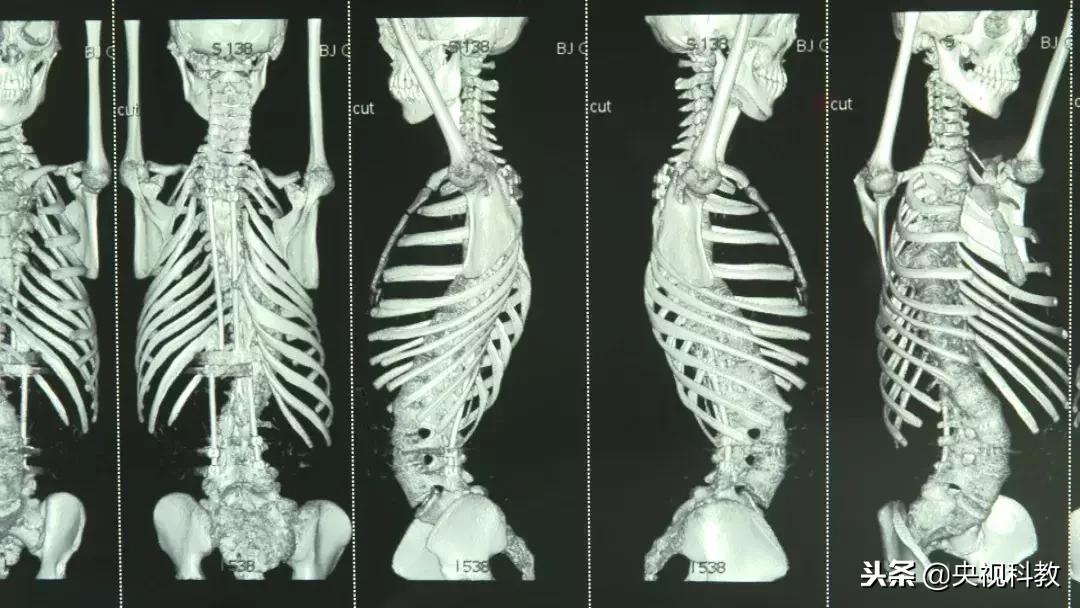

严重的脊椎侧弯不仅是外观上的畸形,更会对胸腹腔的结构产生变化,并发器官功能受损。对患儿的身心都会造成难以弥补的损伤。

如今我国的小儿脊柱侧弯矫正手术已经与国际先进水平无差,但是在潘少川建立儿童骨科之初,由于器械的限制,对这种疾病可以说是束手无策。

潘少川:“上面加一个金属钩子钩到锥板上,往上钩,下面往下钩,这两个钩子之间用一个带齿状的轮子撑开。那时候矫正50%,一半。现在的方法可以矫正90%。”

潘少川在北京儿童医院的手术室里实现了我国小儿脊柱侧弯矫形手术从0到1的突破,开启了我国小儿骨科使用现代化器械完成更高难度手术的先河,这更像是一颗小小的火苗,让无数已经在黑暗中绝望的畸形患儿家长看到了新的希望。